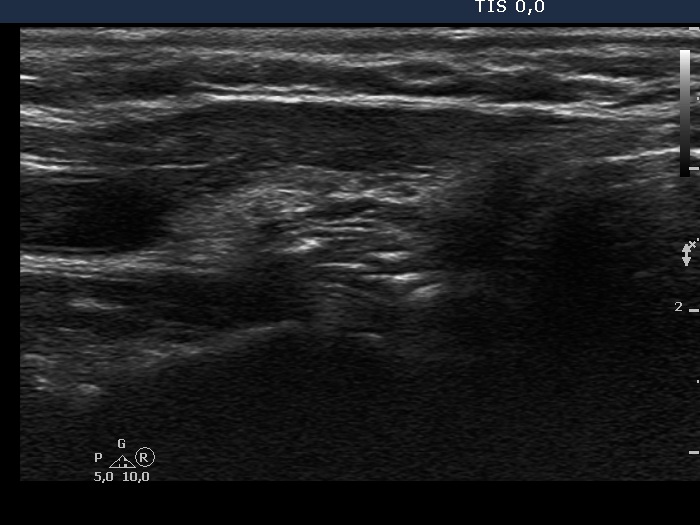

Clinical data: A 41-year-old woman was referred for follow-up examination. She underwent total thyroidectomy and radioiodine therapy for 5 years because of papillary carcinoma. She had no complaints.

Result of blood test: euthyroidism on daily 175 microgram levothyroxine (TSH 0.33 mIU/L).

Ultrasonography. There was no parenchyma according to the thyroid lobes. Connective tissue and muscle fiber have replaced the thyroid tissue, dorsal and ventral part, respectively.